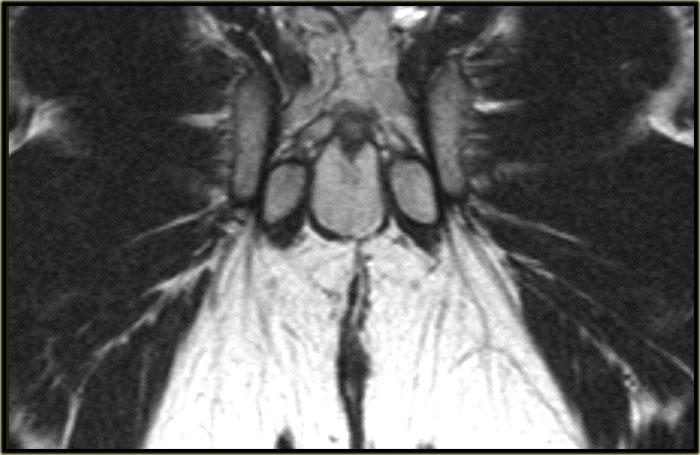

Bên trái là hình ảnh cắt ngang chuỗi xung T2W và T2W kết hợp xóa mỡ của một đường rò xuyên cơ thắt.

Khuyết hổng qua cơ thắt trong và cơ thắt ngoài ở vị trí 6 giờ hiện rõ và nổi bật hơn trên hình ảnh xóa mỡ.